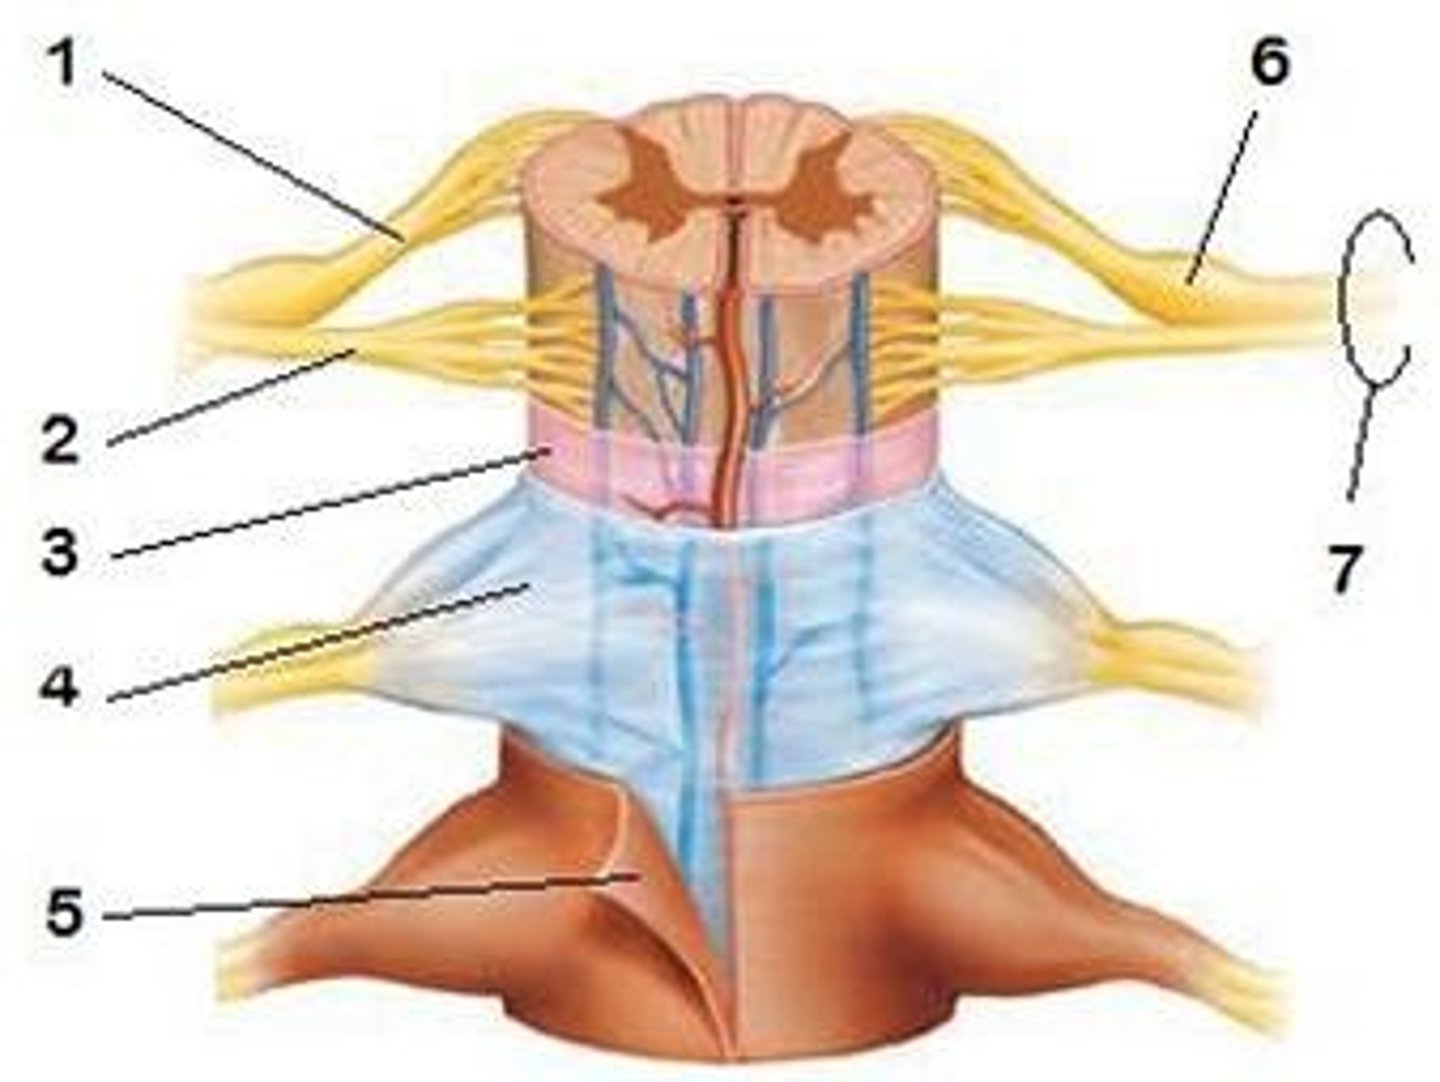

spinal meninges

dura mater, arachnoid mater, pia mater (PAD to protect the spinal cord from deep to superficial)

dura mater (spinal cord)

thick, outermost layer of the meninges; 5 on image

arachnoid mater (spinal cord)

middle weblike layer of the meninges; 4 on image

pia mater (spinal cord)

thin, delicate inner membrane of the meninges; 3 on image

31 pairs of nerves arising from the spinal cord; letter abbreviation for region of spine they originate from; forms where the anterior and posterior roots join; mixed nerves (contain sensory and motor fibers)

posterior (dorsal) rootlets

merge to form a root

posterior (dorsal) root

contains sensory axons

posterior (dorsal) root ganglion

contains cell bodies of sensory neurons

true spinal nerve

anterior root

contains motor axons